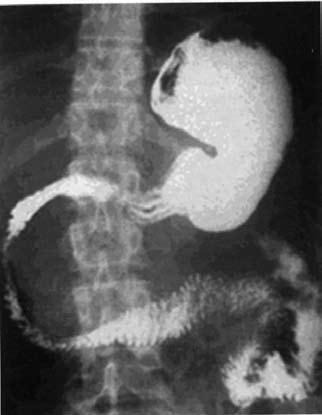

Контрастное исследование желчных путей (холангиография) необходимо, в первую очередь, больным с билиарным ХП или подозрением на таковой. Она осуществляется либо непрямым методом с пероральным или внутривенным введением контрастного вещества, который, к сожалению, не обеспечивает достаточное качество снимков и вообще неприменим у больных с обтурацией желчных путей, либо методом прямого контрастирования. Последнее достигается при уже упоминавшейся РХПГ, а также с помощью чрескожной чреспеченочной пункции желчного пузыря, в том числе под контролем УЗИ, КТ или лапароскопа (рис. 133).

Рис. 133. Ретроградная холангиопанкреа‑тография. Контрастированы желчные протоки и желчный пузырь и главный панкреатический проток. Имеется продленное сужение (симптом «мышиного хвостика») терминального отдела общего желчного протока (панкреатическая часть) и резкое расширение главного панкреатического протока с нечеткостью его контуров